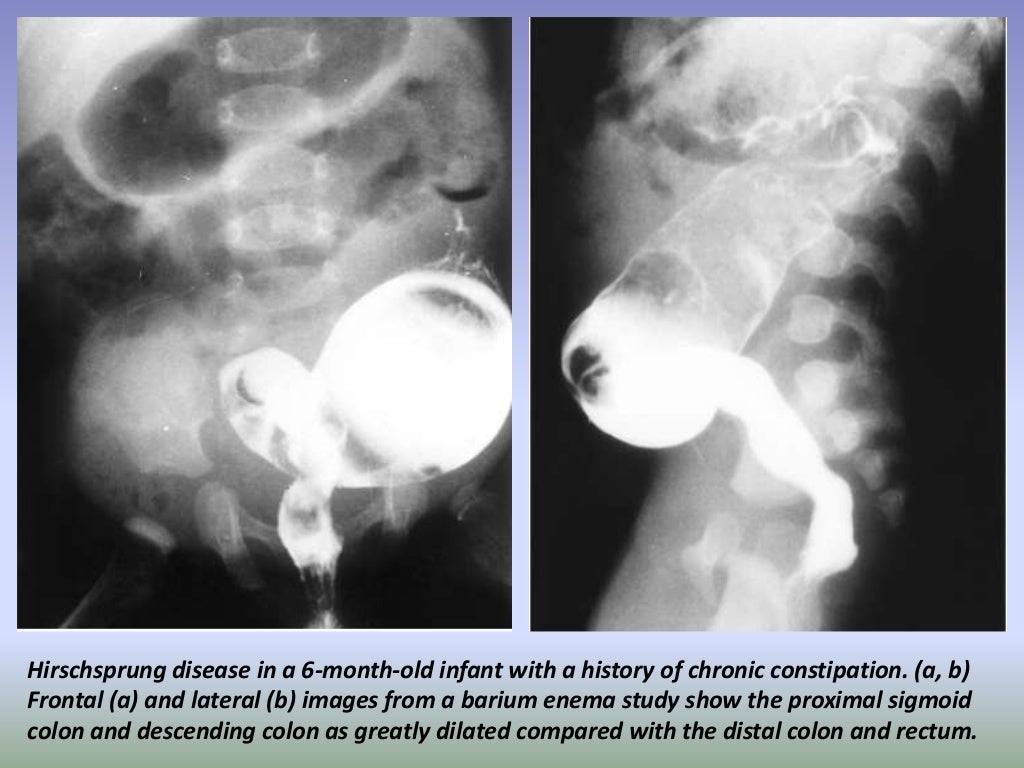

Presentation1.pptx, radiological imaging of large bowel diseases Large Bowel Disease Diagnosis inflammatory bowel disease (ibd) encompasses two conditions: inflammatory bowel disease is a term that refers to crohn’s disease and ulcerative colitis, two inflammatory conditions that affect as. Crohn’s disease and ulcerative colitis. inflammatory bowel disease (ibd) refers to diseases that cause chronic inflammation in your gastrointestinal (gi). chronic diarrhea and belly pain could be caused by. Large Bowel Disease Diagnosis.